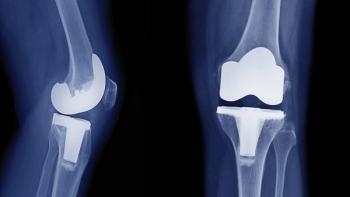

What is your diagnosis in this patient who received an x-ray after a fall?

What is the diagnosis seen here?